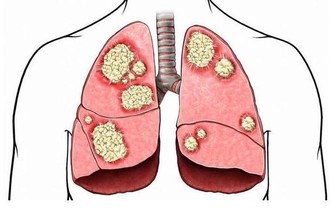

腎積水是一種慢性腎髒病,腎積水的成因是由於腎結石堵塞導致尿液聚積在腎臟內,不能及時排出。如果結石不能及時排出,長時間腎積水,久而久之就會影響到腎臟的功能。